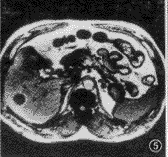

图5,6 患者 女,43岁。右叶血管瘤。反相位序列(TR 128 ms,TE 2.7 ms,翻转角70°)示低信号血管瘤周边环状高信号带(图5),而在同相位(TR 128 ms,TE 5.3 ms,翻转角70°)上病变周边呈等信号(图6)